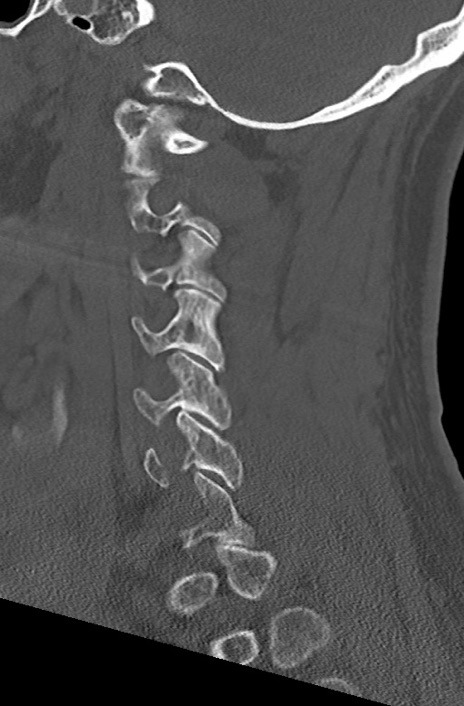

頚椎CT

矢状断像と横断像